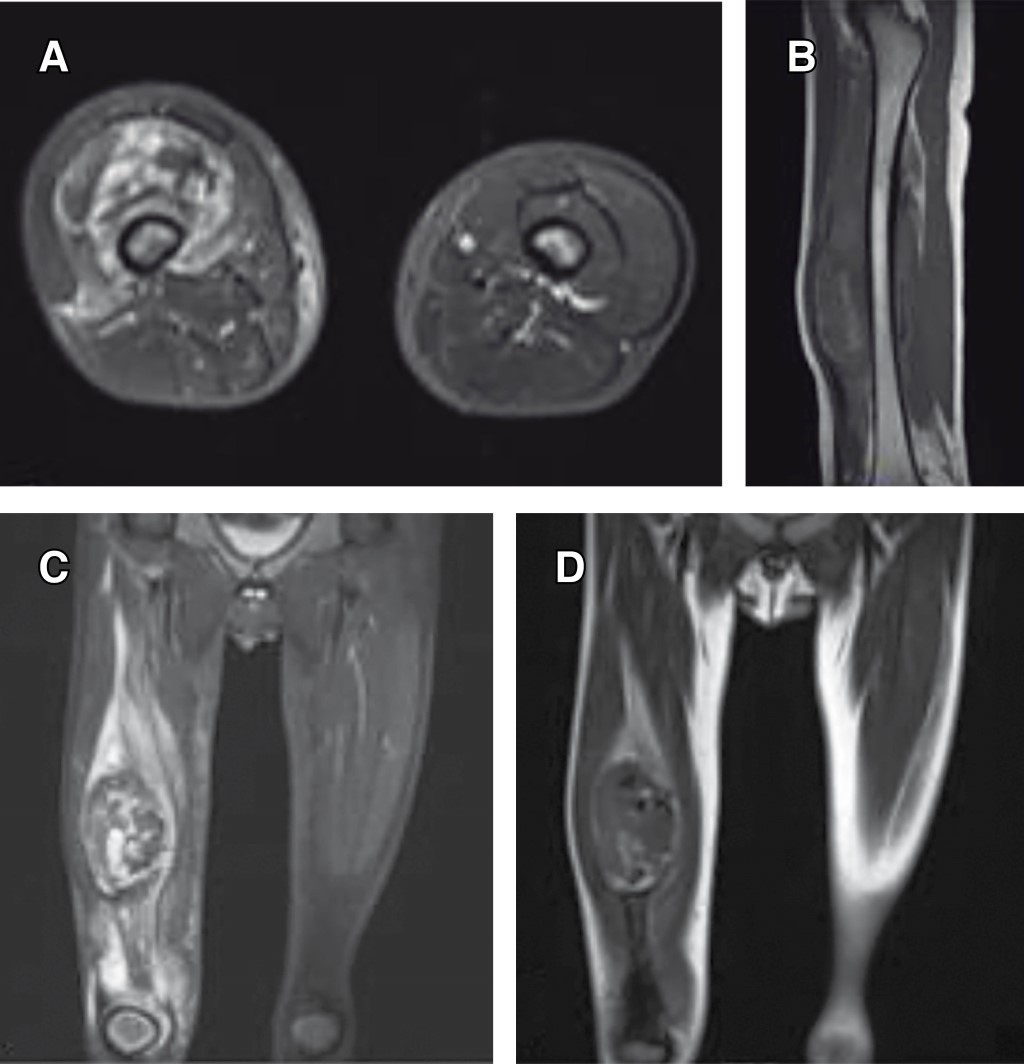

Introduction: myositis ossificans (MO) is described as a non-neoplasic heterotopic bone formation at soft tissues and muscle. It is a rare entity in children, but it must be included within the differential diagnosis of a malignant tumor or an infection. Material and methods: the objective of this retrospective study is to describe three clinical cases of circumscribed myositis ossificans; the first one is a 10-year-old girl with a post-traumatic cervical injury, the second one is an 11-year-old boy with an atraumatic-type distal thigh injury, and the third one is an 8-year-old boy with a post-traumatic right thigh tumor. Results: the diagnosis was made on the basis of the clinical presentation, radiologic imaging and histopathological findings. The results obtained by conservative treatment were good in all cases, with resolution of pain and progressive reduction in size of lesions, without registering complications during follow-up. Conclusion: myositis ossificans is a rare entity, whose diagnosis is usually complex and may require a multidisciplinary team, and whose prognosis is nevertheless favorable.

Figure 2